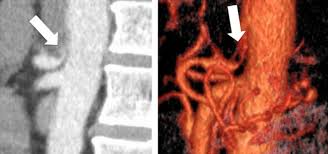

Acute Celiac Artery Compression Syndrome After Extensive Correction Of Sagittal Balance On An Adult Spinal Deformity Semantic Scholar